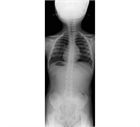

1. 若年者での脊柱変形は、先天性側弯症や思春期に発症する特発性側弯症が多く、通常痛みや機能障害を伴わない場合が多いが、成長に伴い変形が増悪する可能性が高いので見過ごしてはならない。特に特発性側弯症は、思春期の急速な成長期に進行するリスクが高いため、早期発見と適切な介入が重要である。